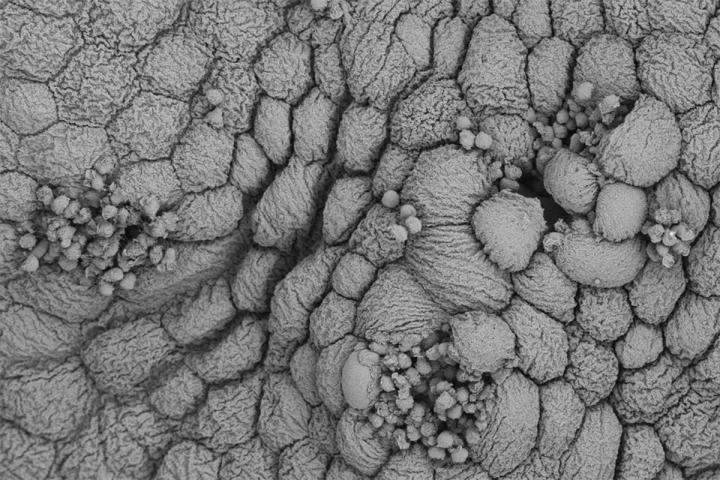

image: White blood cells (small circles) attack infected bladder cells (large circles) in this scanning electron micrograph of a mouse bladder with a bacterial infection. Researchers at Washington University School of Medicine in St. Louis have discovered that an initial urinary tract infection (UTI) triggers changes to immune and other cells in the bladder that can prime the bladder to overreact to bacteria, worsening subsequent UTIs.

Valerie O'Brien